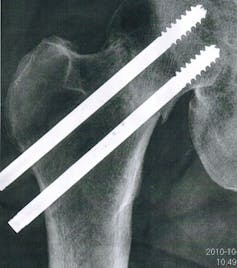

Older people are more likely to suffer a fall and with an ageing population, hip fractures are a growing issue. And new research suggests that the impact of a fall may speed up frailty.

The factors influencing recovery after a hip fracture are poorly understood, but we now know that depression is common and is associated with increased risk of infections and an inability to regain previous levels of physical functioning.

At least half of hip fracture patients never fully recover physically and recorded deaths one year after a hip fracture have been as high as 33%.

We recruited 101 people (81 female) older than 60 who had been admitted to a West Midlands hospital with a fractured hip. All completed questionnaires, structured interviews and provided a blood sample six weeks and six months after their fracture. Another 50 healthy older adults who hadn’t broken their hip were also recruited as control participants. We conducted same-day analysis of neutrophil phagocytosis (its bacteria-eating ability) and neutrophil superoxide production (its bacteria-killing ability) and froze the remainder of the samples to measure for hormones.